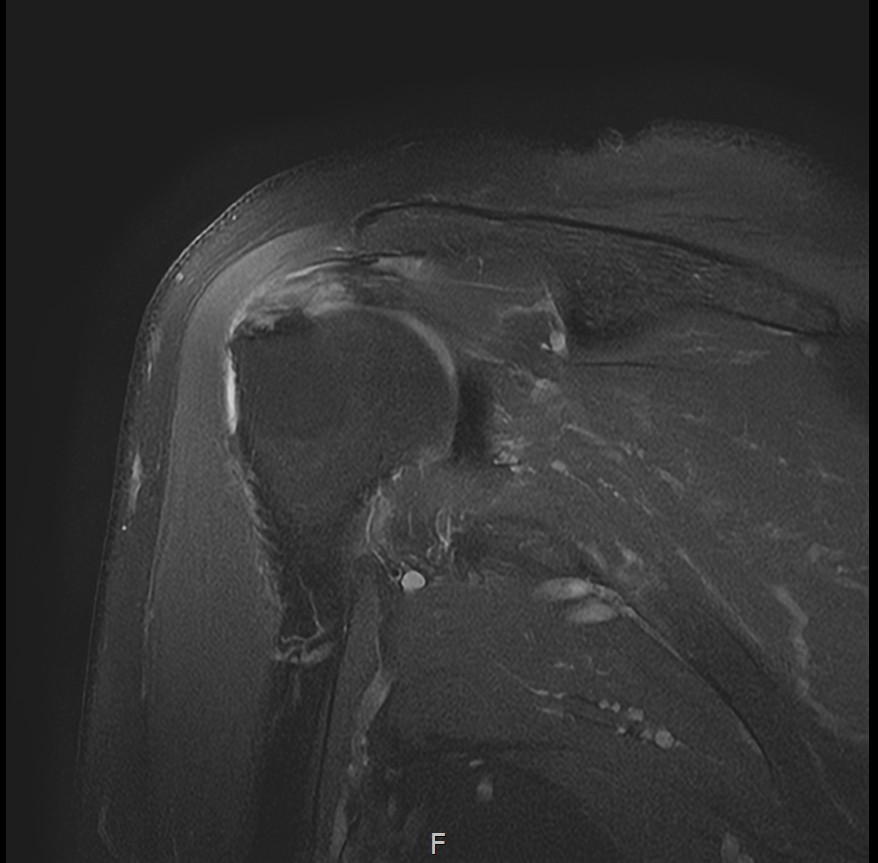

X-ray와 MRI, 초음파 검사를 시행했습니다.

진단 결과:

- ✓석회성건염: 극상건에 약 1.4cm 석회 (휴지기)

- ✓회전근개 관절면측 부분파열: 약 40%

두 가지 문제가 동시에 있었습니다.

- ✓관절면측 부분파열: 약 35%

- ✓근육 위축이나 지방 변성은 없음 (젊은 나이)

10주 후 초음파:

봉합 부위가 정상 인대처럼 하얗게 재생되어 있었습니다. 골수자극의 효과로 예상보다 빠른 재생이 확인되었습니다.